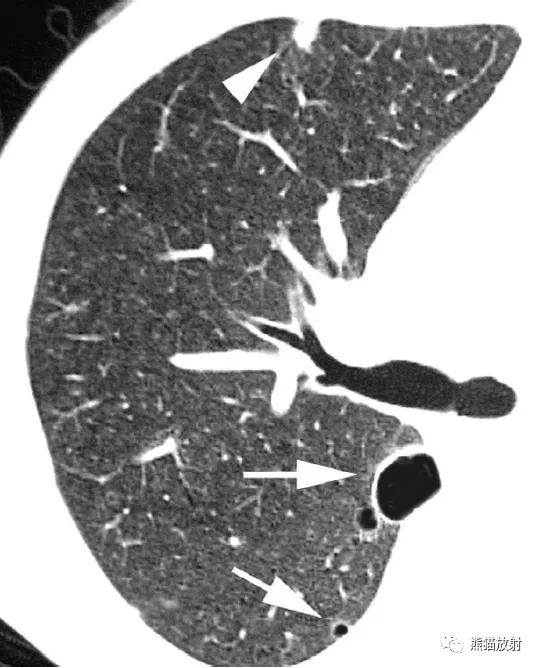

↑ 卡氏肺孢子菌肺炎和囊肿 Pneumocystis pneumonia and cysts

37岁男性,艾滋病患者。CT示广泛分布的磨玻璃密度影,多发囊肿(肺气囊)和结节影。诊断为卡氏肺孢子菌肺炎。